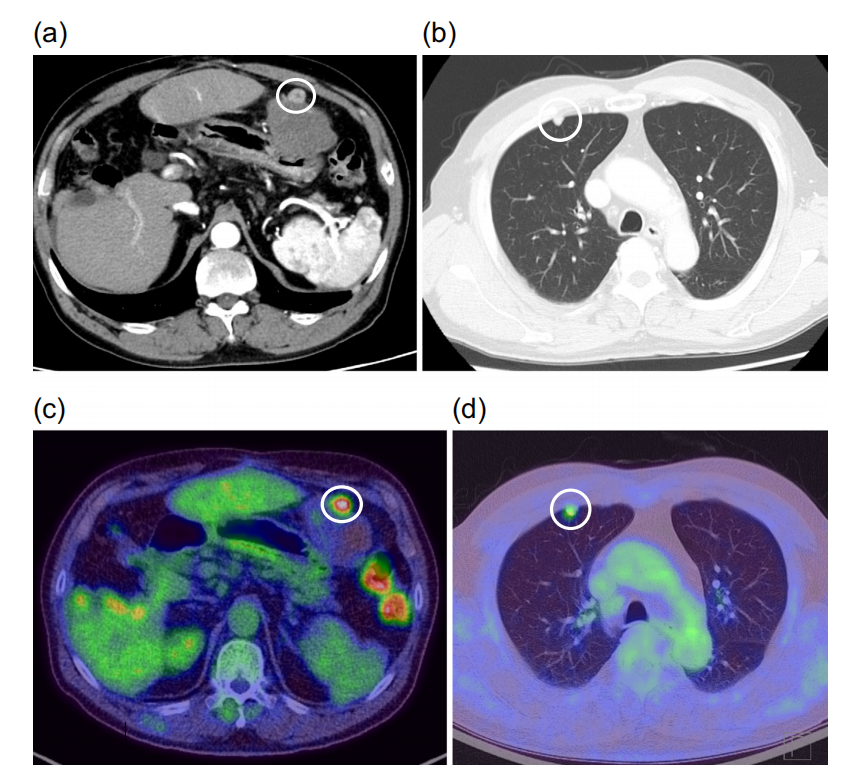

在瑞戈非尼治疗19个月后,他接受艾尔巴韦和依巴司韦格佐普韦片治疗HCV,并在治疗后12周获得持续病毒学应答(SVR)。瑞戈非尼治疗22个月后,CT显示新的肺转移和腹膜播散增强结节,大小为10mm。PET/CT显示腹膜播散性高代谢病变,最大标准化摄取值(SUVmax)为5.6,而右肺转移灶为2.4。

腹膜播散行手术切除,病理结果为HCC转移。第三次手术后2个月,CT显示肝3段HCC复发,肺转移灶的大小没有变化。HCC为单个小于20mm的结节,接受射频消融(RFA)治疗。肺部转移采用胸腔镜手术(VATS)治疗。距离肝细胞癌破裂已经过去了4年零6个月,基于这些治疗,病人仍然存活。